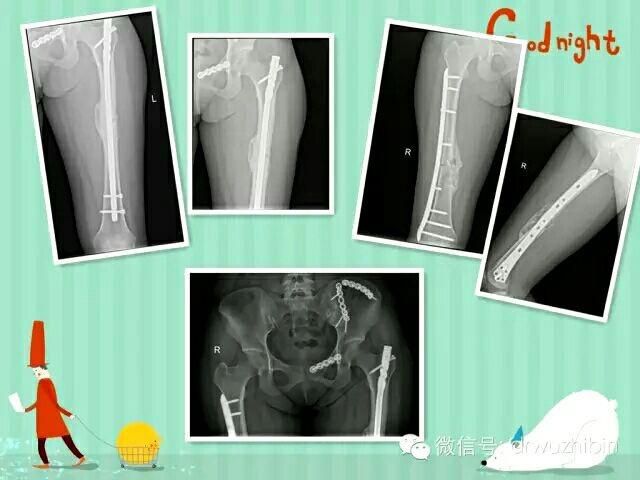

以下是近期收治的一名骨盆多發性骨折合并泌尿系損傷、雙側股骨幹骨折的患者,術後康複良好。

更加規範的搶救流程,更加合理使用各種治療器械,更好的療效,是我們追求和努力的目标!